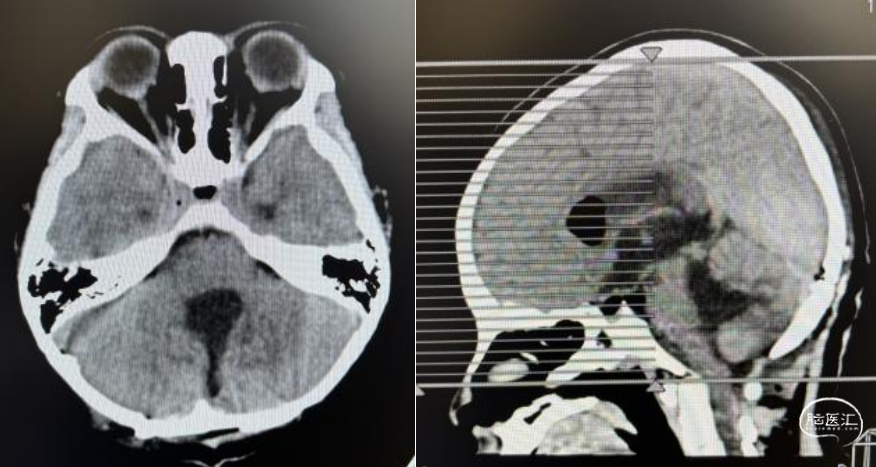

男,10岁,间断头痛伴头晕2月入院。

体查:神清,步态不稳。

头部MRI显示:小脑蚓部可见团块状混杂信号灶,大小约46mm*39mm,以等T1等T2信号灶为主,其内可见多发小囊变,增强后可见不均匀强化,四脑室扩张,小脑扁桃体下移,幕上脑室扩大并间质水肿。

综合分析患儿的术前资料,诊断考虑髓母细胞瘤可能性大,手术指征明确。术后病理证实为髓母细胞瘤。髓母细胞瘤起源于小脑,可在小脑蚓部及半球发生。其分型主要依据病理检查结果。其组织学分型有:经典型、促纤维增生/结节型、广泛结节型和间变/大细胞型,由于其与预后对应性差。目前临床上更多采用分子分型,髓母细胞瘤的分子分型包括:WNT型、SHH型、Group3及Group4。在此基础上还有进一步分型,此处不做讨论。